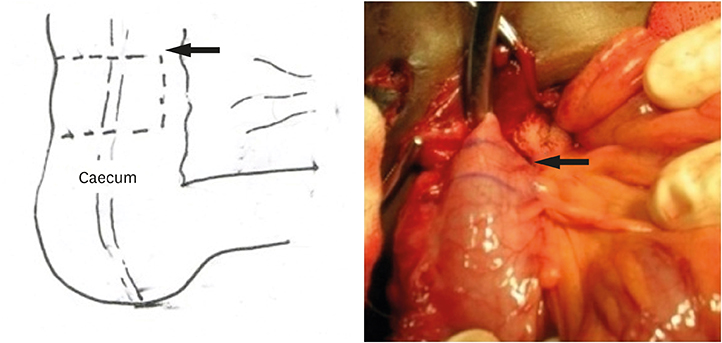

1) Cecal flap

The flap was based on the anti-mesenteric blood supply, junction of caecum and colon was identified, a flap of width 1.5 cm and the length of 5 cm were marked (

Figs. 1,

2,

3). This flap was raised over stay sutures; a tube was constructed over 10 F catheter with 4-0 vicryl-interrupted sutures. Single row of sutures was placed. The defect in the colon was closed in two layers. The tubularized flap was turned on itself and imbrications done to create anti-reflux mechanism.

Fig. 1Marking of cecal flap (black arrow), size 1.5×5 cm.

Fig. 2Creation of cecal flap.